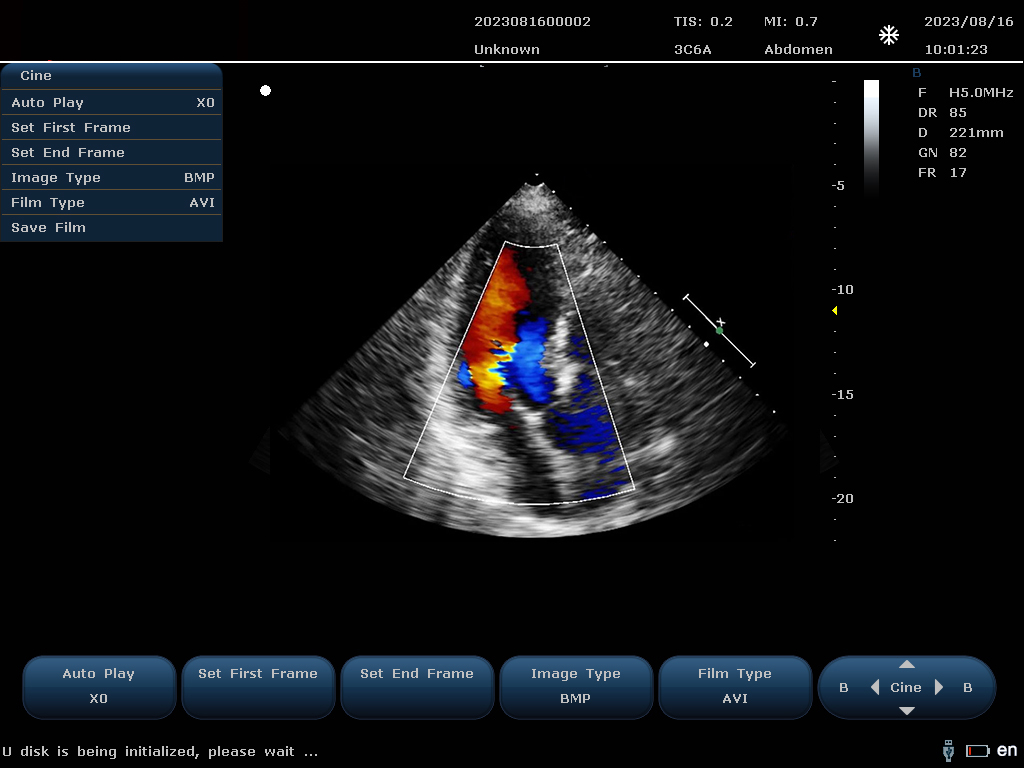

设备通过检测这些频移信号,并利用复杂的信号处理技术,包括傅立叶变换等,分析血流的方向、速度和分布。彩色编码后,血流信息被叠加在传统的黑白超声二维图像上,形成彩色多普勒图像,直观显示血流动态。

最终,这些信息转化为图像显示在屏幕上,医生可以根据图像中血流的颜色(通常红色代表血流朝向探头,蓝色代表远离探头)和亮度来判断血流的性质和异常情况,如血流速度增快可能指示狭窄,无血流区域可能意味着阻塞等。